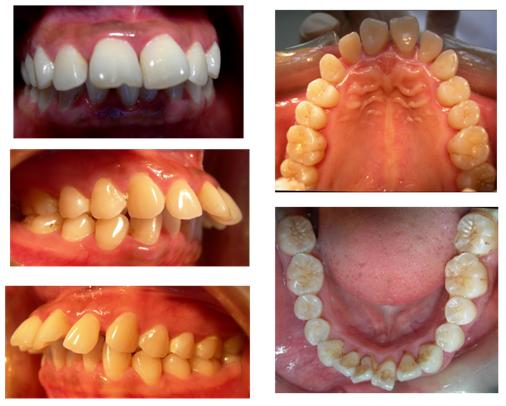

苏牧大夫向李女士介绍了与她情况类似的一位患者的治疗过程。该患者也是上下牙列不齐,同时上前牙唇倾,正面观嘴唇外翻、开唇露齿,侧面观亦不协调,上唇突出。虽然患者的上下牙列均拥挤不齐,但考虑到面型及上下前后牙的咬合关系,该患者拔除了上颌左右的第一前磨牙来进行矫治,通过内收上颌前牙,排齐上下牙列,建立正常的前牙覆合覆盖,消除了牙周创伤因素,牙列咬合关系与口周肌肉建立平衡,也极大改善了患者的容貌。

矫正牙齿是否拔牙需要经过缜密的诊断分析,像上面展示的病例中虽然患者上下牙列都存在拥挤不齐,但通过综合评估患者的正侧容貌、骨面型及上下牙列之间的咬合关系,从而选择在上颌拔除左右第一双尖牙,下颌不拔牙矫治的方案,不仅明显提升了患者的颜值,建立了稳定平衡的咬合功能,同时也有效降低了正畸治疗的时间和风险。